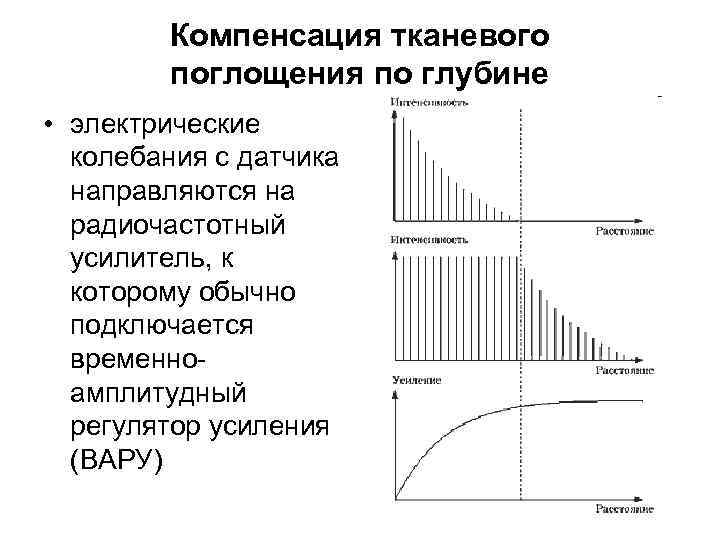

Компенсация тканевого поглощения по глубине • электрические колебания с датчика направляются на радиочастотный усилитель, к которому обычно подключается временноамплитудный регулятор усиления (ВАРУ)

Компенсация тканевого поглощения по глубине • электрические колебания с датчика направляются на радиочастотный усилитель, к которому обычно подключается временноамплитудный регулятор усиления (ВАРУ)